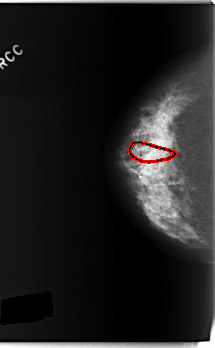

FILE: C_0232_1.RIGHT_CC.OVERLAY

TOTAL_ABNORMALITIES 1

ABNORMALITY 1

LESION_TYPE CALCIFICATION TYPE FINE_LINEAR_BRANCHING DISTRIBUTION SEGMENTAL

ASSESSMENT 5

SUBTLETY 4

PATHOLOGY MALIGNANT

TOTAL_OUTLINES 1

BOUNDARY

C_0232_1.RIGHT_CC